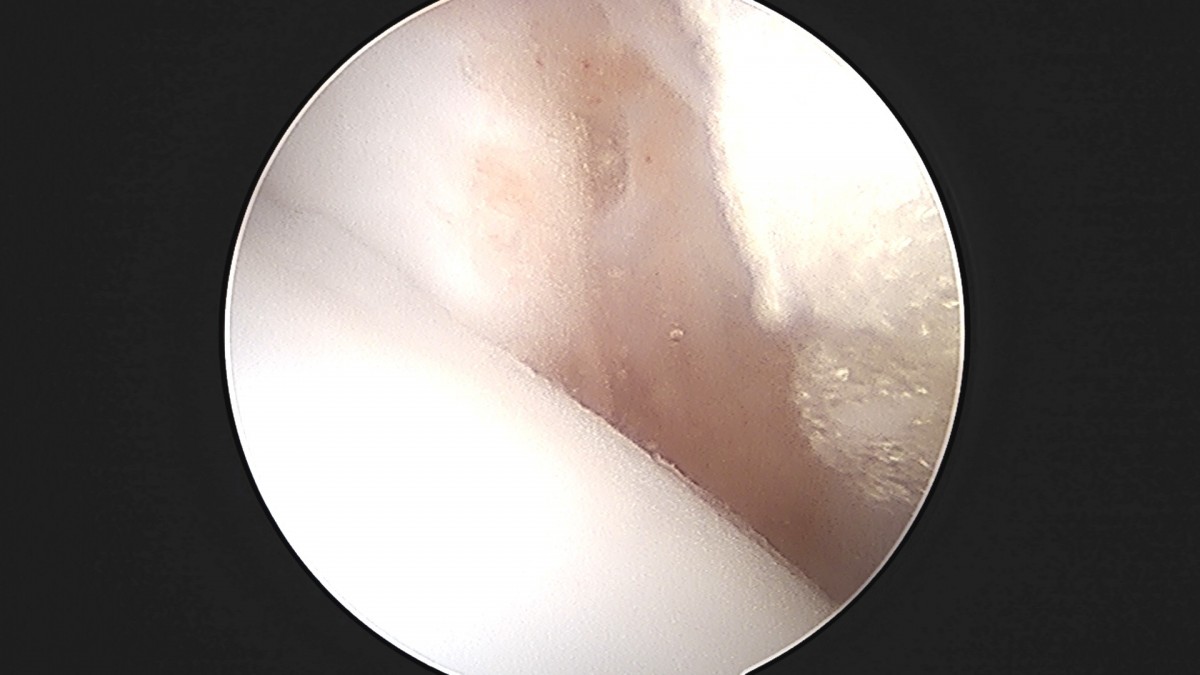

정지영원장님 발목 인대 봉합술 채이O 환자

작성자 최고관리자 댓글 0건 조회 718회 작성일 25-09-16 17:02